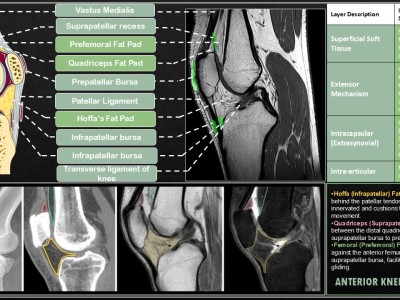

ECR26 / C-26650

Mapping the Spectrum of Knee Fat Pad Lesions : From Anatomy to Advanced Pathologies P. Parichha, A. R Patil, G. Pradeep, D. Rai; Bengaluru/IN -